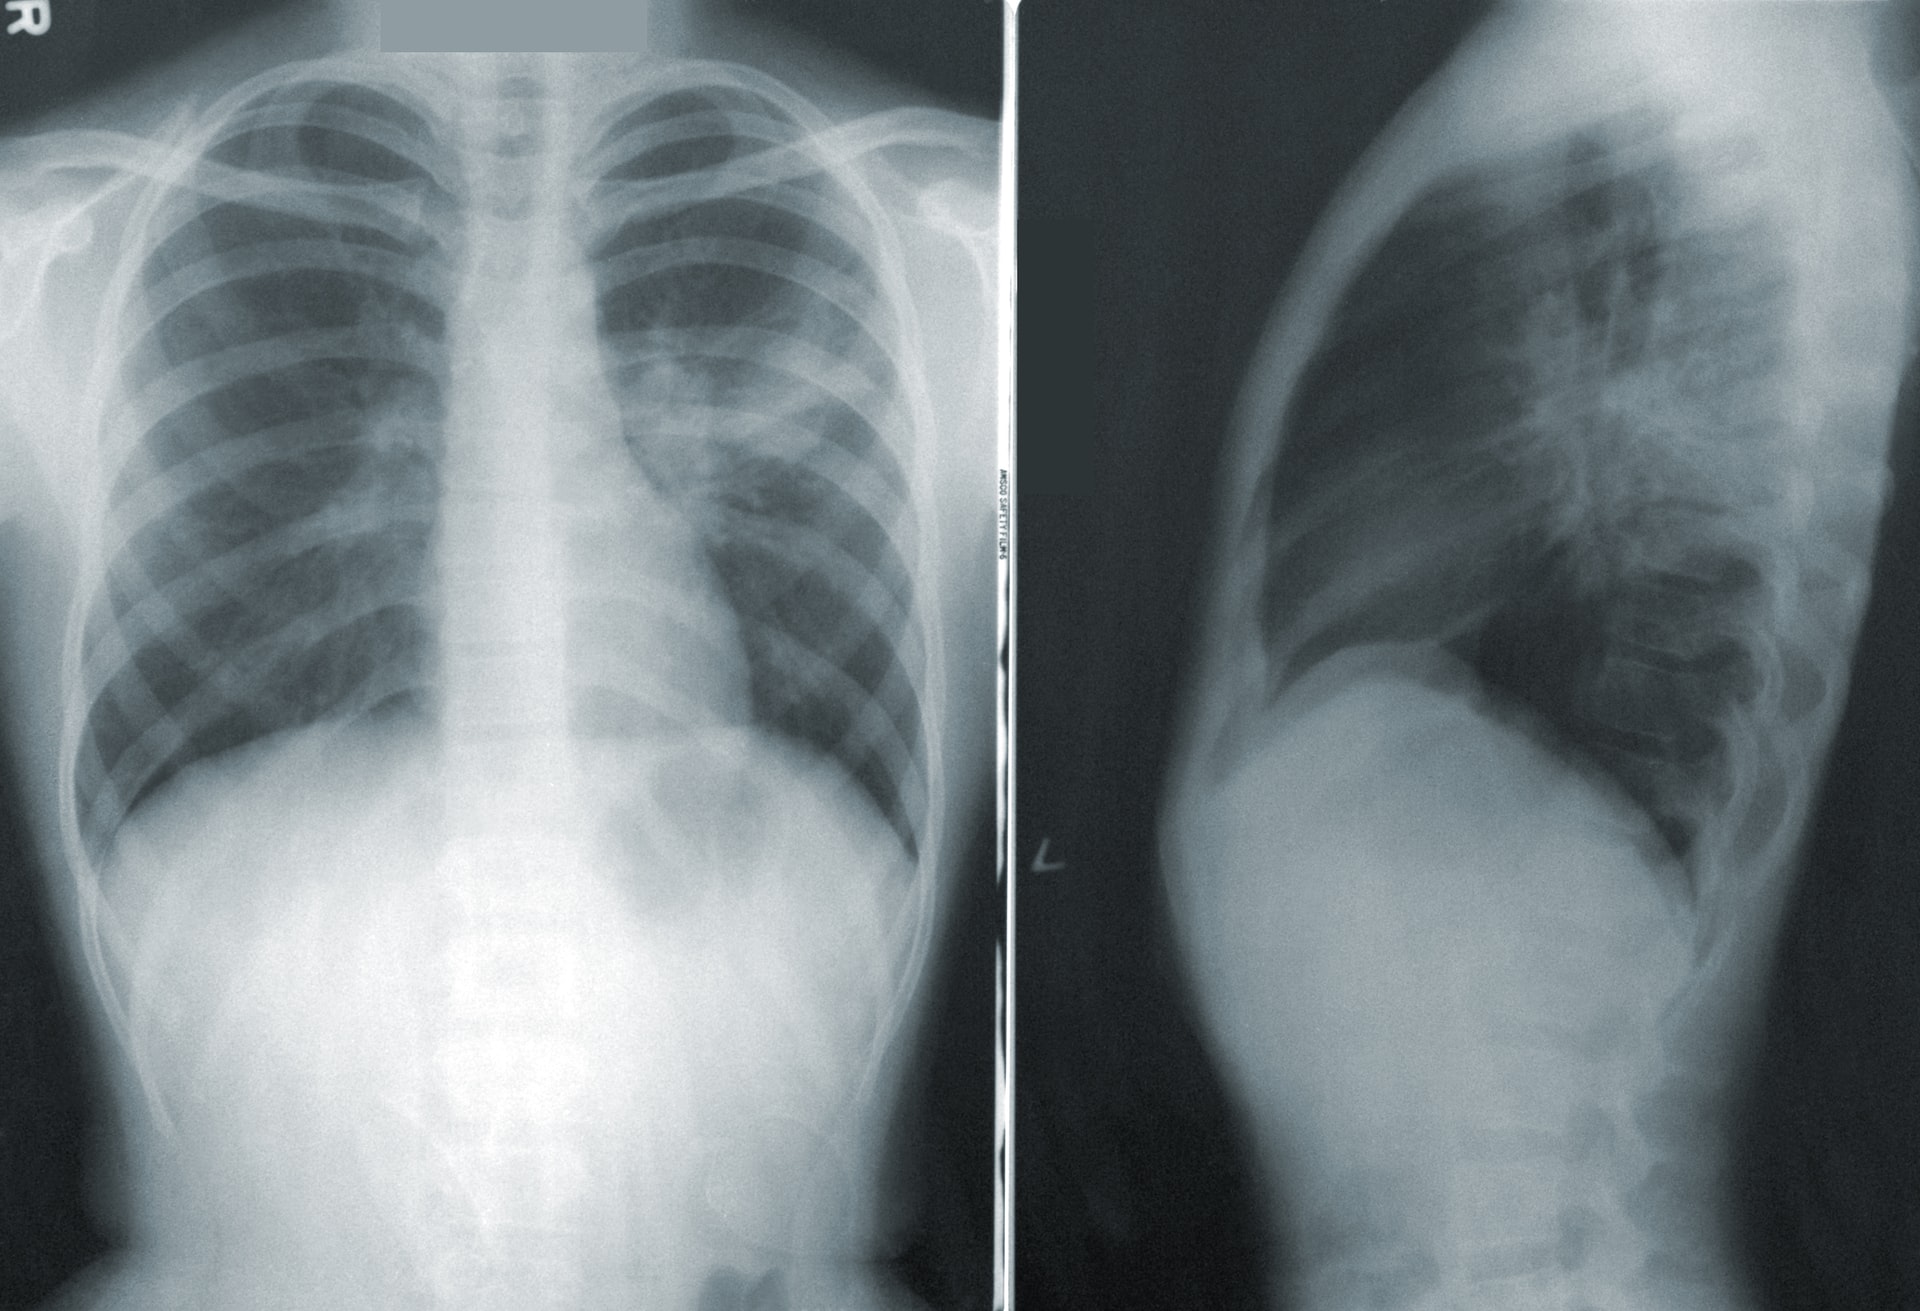

Швейцарские ученые выявили осложнения, связанные с тяжелыми формами Covid-19: даже спустя 4 месяца после болезни легкие поглощают в среднем на 20% меньше кислорода, чем у полностью здорового человека.

В рамках исследования «Swiss national Covid-19 lung study», проведенного под руководством Университетского госпиталя Берна, ученые проанализировали данные о 113 больных, у 66 из которых была диагностирована тяжелая форма заболевания, у остальных – легкая или умеренно тяжелая. Тесты уровня поглощения кислорода включали, среди прочего, рентгенографию легких после шестиминутной ходьбы. Кроме того, были учтены такие факторы, как индекс массы тела, табакокурение, возраст, перенесенные ранее заболевания и т.д. «Swiss national Covid-19 lung study» - первое исследование национального масштаба, посвященное состоянию легких после Covid-19. В работе приняли участие девять центров пульмонологии, расположенные в Тичино, Романдии и немецкоязычных кантонах.

В целом, систематическая рентгенография грудных клеток пациентов с Covid-19 позволила выявить присутствие изменений в легких. Врачи подчеркивают необходимость собрать больше информации о влиянии этой болезни на легкие в средне- и долгосрочной перспективе. Авторы исследования пришли к выводу, что пациенты нуждаются в долгой реабилитации и терапии после того, как пройдет острая стадия заболевания, так как последствия наблюдаются не только в легких, но и в сердечно-сосудистой системе. Доступные сегодня данные и информация, которая будет собрана в рамках последующих исследований, позволят обеспечить максимально эффективное лечение пациентов, заразившихся новым коронавирусом.